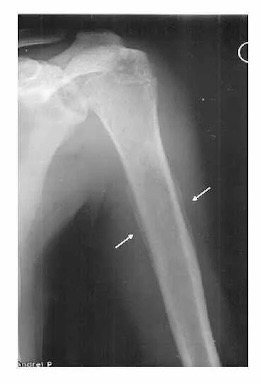

Рентгенография служит методом первичной диагностики — она позволяет заподозрить сам факт опухолевого процесса в костях. Существуют типичные рентгенологические признаки злокачественных опухолей костей. Среди них, в том числе, нарушение целостности внешнего слоя кости — так называемый «козырек» Кодмана, особенно характерный для остеосаркомы, а также «луковичный» периостит, который чаще наблюдается при саркоме Юинга.

Луковичный периостит при саркоме Юинга